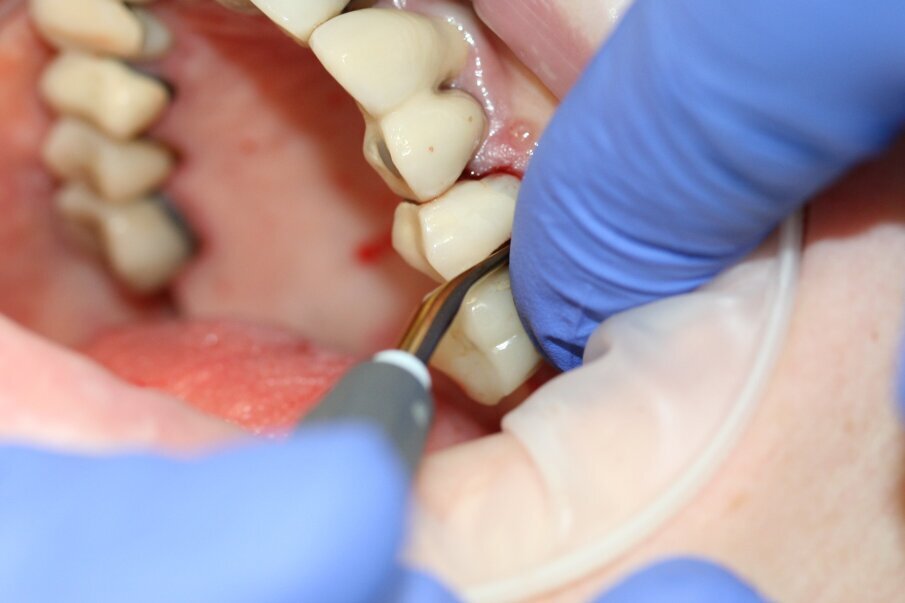

Fig. 4: The tooth was luxated with Luxator P4 (dual edge, lilac).

Fig. 5: The tooth was luxated with Luxator P4 (dual edge, lilac).

Luxator P4, with its extremely sharp dual-edge blade, was used at the beginning, followed by Luxator P1 once more space had been created. Although the blades of these sophisticated instruments are reinforced with a titanium coating, they should only be used to cut the periodontal ligament and never to elevate the tooth.